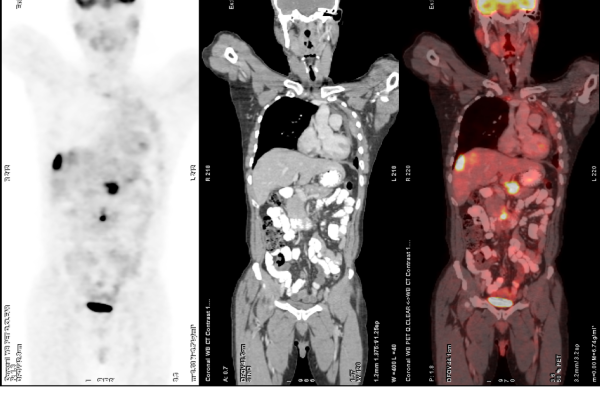

FDG-PET-CT

FDG PET-CT is one of the most advanced and widely used imaging techniques in modern medicine, especially for cancer evaluation. It works by detecting areas of increased glucose metabolism in the body, which is a common characteristic of active cancer cells, infections, and certain inflammatory conditions. By combining the metabolic insights from PET with the anatomical detail of CT, FDG PET-CT offers exceptional accuracy in locating and characterizing disease. This scan plays a critical role in the diagnosis, staging, and treatment planning of a wide range of cancers. It also helps assess how well a tumor is responding to therapy and can detect recurrence at an early stage, often before it becomes visible on conventional scans.

Key Applications:

• Initial staging of various cancers (lung, breast, lymphoma, etc.)

• Monitoring treatment response

• Detecting tumor recurrence or metastasis

• Whole-body oncological assessment